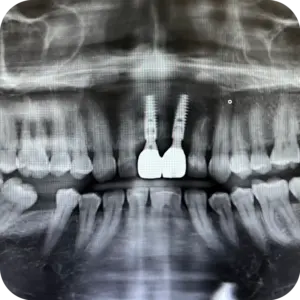

El paciente acudió para rehabilitar las piezas 8 y 9, buscando recuperar funcionalidad y armonía en una zona clave de su sonrisa. Tras la evaluación clínica, se planificó una cirugía guiada y precisa para asegurar estabilidad y proyección estética adecuada.

Se colocaron implantes en ambas piezas con pilares personalizados, logrando una base firme para su futura rehabilitación. El procedimiento fue realizado bajo protocolo quirúrgico controlado, con seguimiento radiográfico posterior.

Hoy cuenta con una solución estable y planificada al detalle, que permitirá devolverle seguridad, funcionalidad y una sonrisa natural.